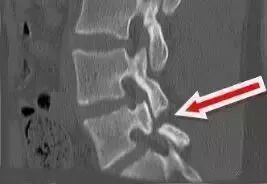

指腰椎某节椎体向前或向后发生移位,从而出现一系列症状,如下图所示。

腰椎滑脱的病因包括急性外伤、先天发育不良、慢性劳损、腰椎退变及病理性骨折等因素。

当滑脱的腰椎导致神经根受到牵拉时,患者会出现下肢疼痛麻木症状。滑脱严重时,马尾神经受到牵拉、压迫,患者可能出现下肢乏力、鞍区麻木及大小便功能障碍等马尾神经症状。卧床休息后,症状可减轻或消失,但劳累、扭伤后,站立、弯腰时,可能导致症状加重。